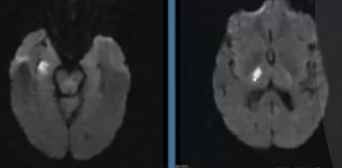

What vessel(s) caused this stroke?

Anterior Choroidal Artery

Interesting pearl: The homonymous hemianopsia appears as this:

Occlusion of which vessel(s) cause this stroke?

Artery of Percheron